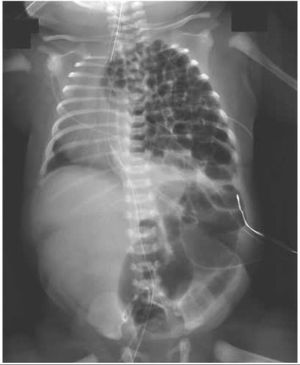

#SURGERY This female infant was delivered by planned cesarean section at 36 weeks of gestation. What is the most likely prenatal diagnosis? A. Duodenal atresia B. Intussusception C. Hirschsprung's disease D. Congenital diaphragmatic hernia

Congenital diaphramatic hernia

A diaphragmatic hernia occurs when one or more of your abdominal organs move upward into your chest through a defect (opening) in the diaphragm. This kind of defect can be present at birth or acquired later in life. It’s always a medical emergency and requires prompt surgery to correct